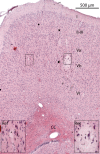

Transcranial magnetic stimulation (TMS) is a widely used non-invasive tool to study and modulate human brain functions. However, TMS-evoked activity of individual neurons has remained largely inaccessible due to the large TMS-induced electromagnetic fields. Here, we present a general method providing direct in vivo electrophysiological access to TMS-evoked neuronal activity 0.8-1 ms after TMS onset. We translated human single-pulse TMS to rodents and unveiled time-grained evoked activities of motor cortex layer V neurons that show high-frequency spiking within the first 6 ms depending on TMS-induced current orientation and a multiphasic spike-rhythm alternating between excitation and inhibition in the 6-300 ms epoch, all of which can be linked to various human TMS responses recorded at the level of spinal cord and muscles. The advance here facilitates a new level of insight into the TMS-brain interaction that is vital for developing this non-invasive tool to purposefully explore and effectively treat the human brain.